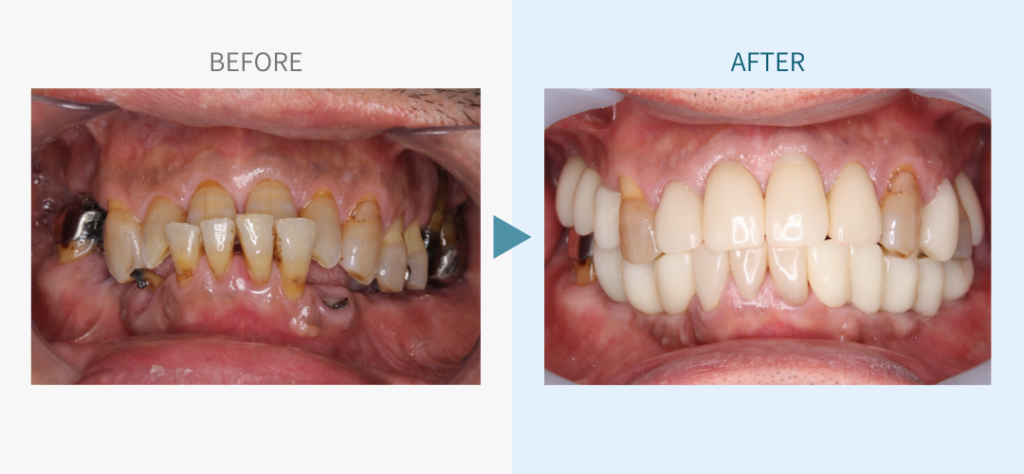

デンタルチームジャパンでは、サイナスリフト(上顎洞底挙上術)や骨造成など、他院で「骨が足りない」と断られた難症例にも対応しています。

私たちは、難症例に関する治療法を学会でも発表しており、その豊富な実績と技術力が評価され、全国から患者様が来院いただいております。

こちらではその一部の症例についてご紹介します。